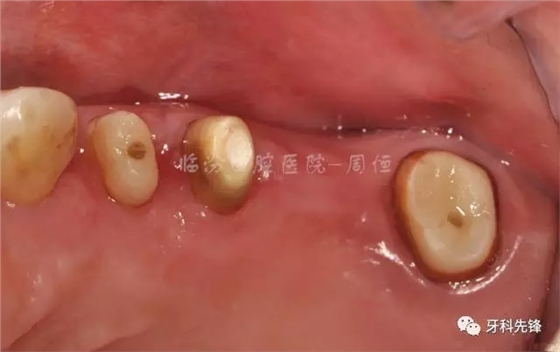

圖4拆除原修復(fù)體牙列照

640.webp (5).jpg

圖9去除腐質(zhì)口內(nèi)照

640.webp (13).jpg